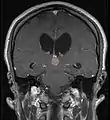

ورم الغدة الصنوبرية

ورم الغدة الصنوبرية Pinealoma هو ورم حميد عادة في الغدة الصنوبرية. تنتج الغدة الصنوبرية هرمون الميلاتونين الذي يلعب دوراً في تنظيم إيقاع الحياة اليومي. وقد يُعطّلُ ورمُ الغدة الصنوبرية إنتاجَ هذا الهرمون، و يسبب الأرق.[2]

التشخيص

من بين الأنواع المختلفة لأورام الغدة الصنوبرية، يبرز النوع الأكثر تفضيلاً عند التشخيص و هو ورم الخلية الصنوبرية.[7]